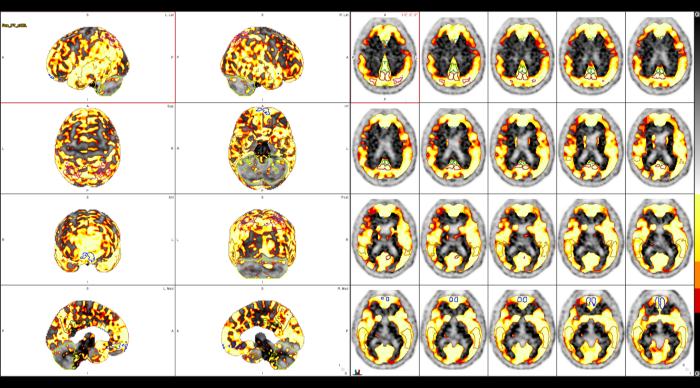

Οι κυριότερες εφαρμογές της αφορούν την ογκολογία, τη νευρολογία και, σε μικρότερο βαθμό, την καρδιολογία, ενώ συνεχώς αναπτύσσονται νέες χρήσεις σε άλλες ιατρικές ειδικότητες.

Στο Κέντρο PET/CT πραγματοποιούνται εξειδικευμένες εξετάσεις που καλύπτουν ένα ευρύ φάσμα κλινικών εφαρμογών στη σύγχρονη Πυρηνική Ιατρική. Ανάλογα με το είδος του προβλήματος και τη φύση της νόσου, χρησιμοποιούνται διαφορετικά ραδιοφάρμακα για τη μελέτη συγκεκριμένων βιολογικών μηχανισμών.